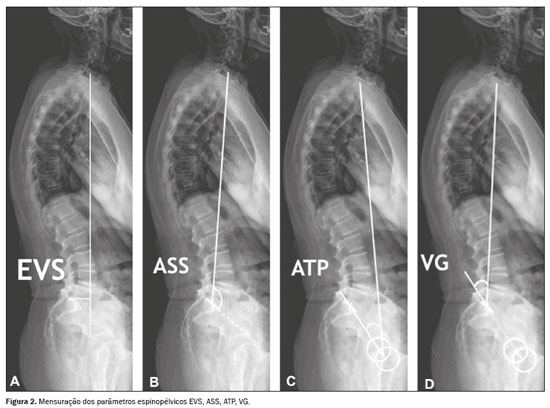

Para mensurar os parâmetros espinopélvicos e ângulos das curvaturas vertebrais foi utilizado o software Surgimap (Nemaris Inc., New York, NY, EUA). Os seguintes parâmetros foram avaliados: inclinação sacral (IS); versão pélvica (VP); incidência pélvica (IP); lordose lombar (LL); cifose torácica (CT); eixo vertical sagital (EVS); ângulo espinossacral (ASS); ângulo T1 pélvico (ATP) e versão global (VG), conforme mostrado nas Figuras 1 e 2. A IS corresponde ao ângulo formado entre a placa da extremidade superior de S1 e a linha horizontal. A VP corresponde ao ângulo formado entre uma linha vertical que se origina no centro da cabeça femoral e uma linha que parte do centro da cabeça femoral para o ponto médio da placa terminal de S1. A IP corresponde ao ângulo formado pela perpendicular ao platô sacral e a linha que conecta o ponto médio deste com o centro de rotação femoral. A LL é a medida do ângulo de Cobb do platô superior de S1 até o platô superior de L1. A CT é a medida do ângulo de Cobb do platô inferior de T12 até o platô superior de T1. O EVS é a medida da distância horizontal entre a linha de prumo de C7 e a linha vertical que passa pelo ponto posterossuperior de S1. O ASS corresponde ao ângulo formado entre a linha que passa do centro de C7 ao centro da placa terminal de S1 e a superfície da placa terminal sacral. O ATP é o ângulo obtido por uma linha formada do centro geométrico das cabeças femorais ao centro do corpo vertebral T1 e uma linha do centro geométrico das cabeças femorais ao centro da placa terminal superior de S1. A VG é definida como o ângulo formado por uma linha do centro da placa final superior sacral ao centro do corpo vertebral C7 e uma linha do centro geométrico das cabeças femorais ao centro da placa terminal sacral(15). Os contornos das cabeças femorais foram marcados e foram traçadas linhas adjacentes ao platô superior de S1, platô superior de L1, platô inferior de T12, platô superior de T1 e platô inferior de C2. A partir dessas marcações, o software calculou automaticamente os parâmetros espinopélvicos e as curvaturas vertebrais.